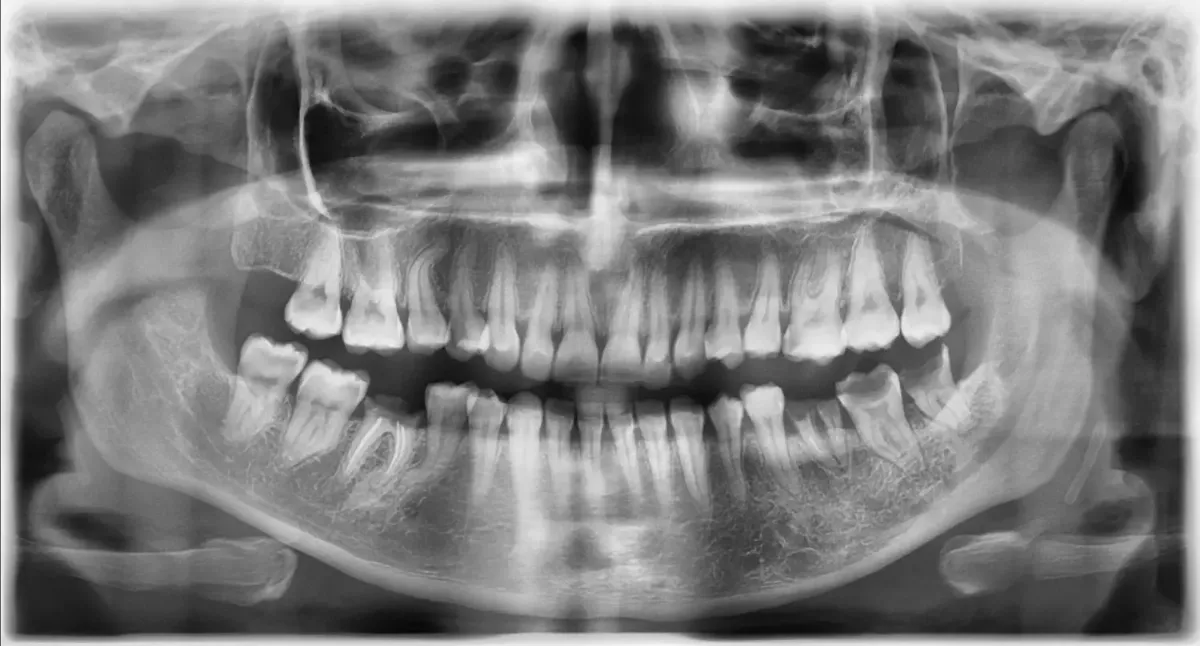

Voor complexe pijnklachten en implantaten kunnen we nu ook tandheelkundige CT-scans maken

Als we controle-/röntgenfoto's voorstellen, horen we regelmatig "als u denkt dat het nodig is?!"...